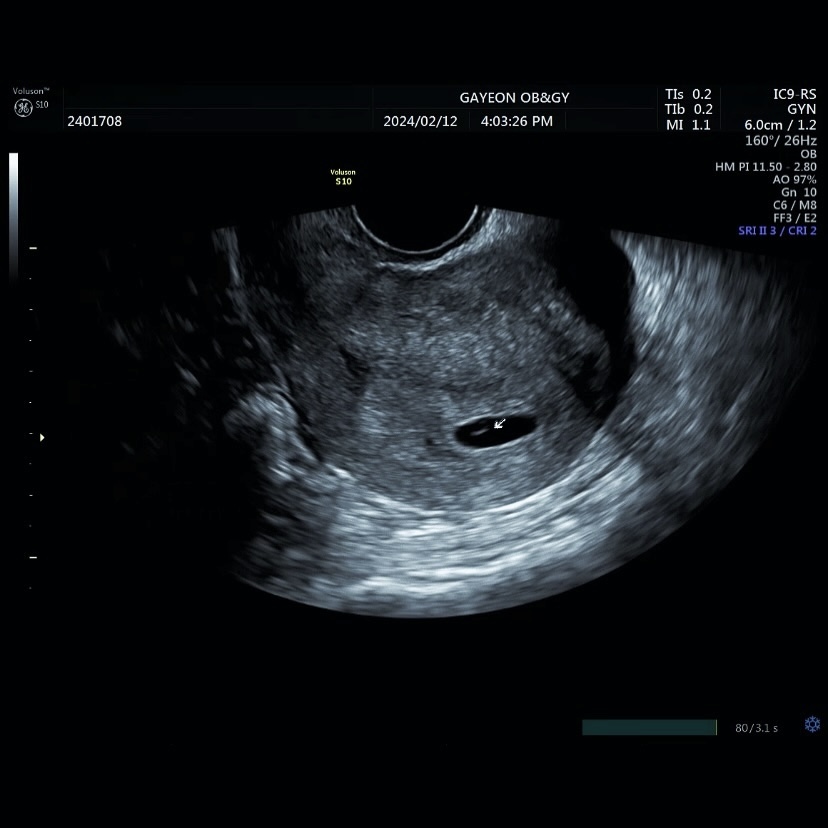

다음날 찾은 병원,

아직 수치는 낮았지만

분명 제 안에 누군가가 찾아왔다는 걸 확인했어요.